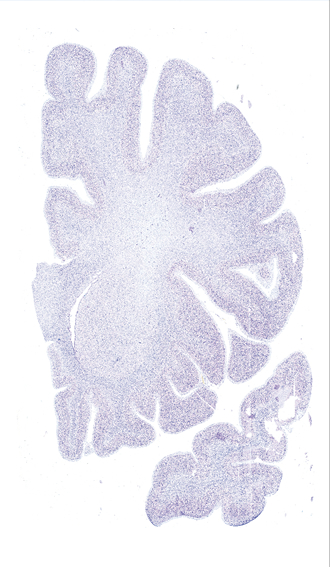

Hi-Resolution Sections · Cells (Nissl Staining) · Virtual Microscopy

Frontal sections (Nissl) from the Atlas Brain:

Slice ID:

r2-0420

Plate NR:

12

Position:

-15,4 mm